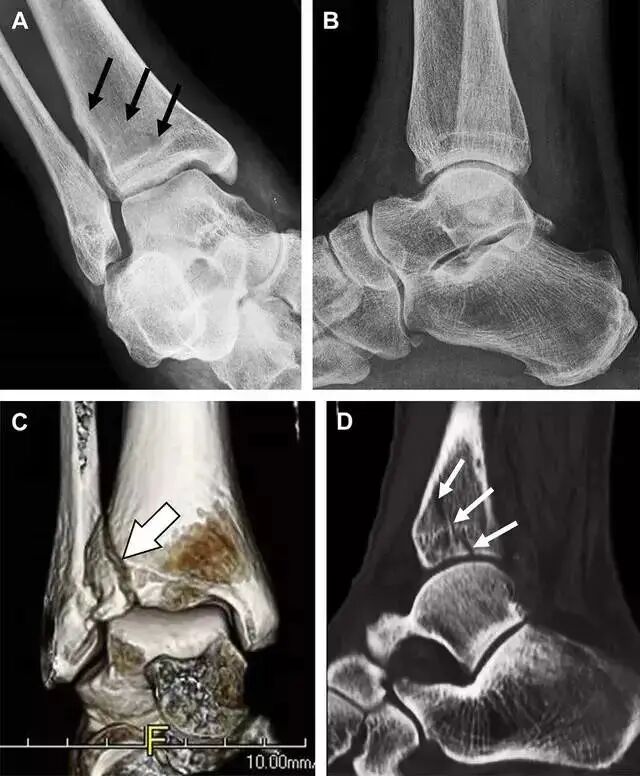

17胫骨结节骨折

Tillaux 骨折,是足外旋外展时,胫腓前韧带牵拉引起的一种胫骨结节撕脱性骨折。斜位片上可见典型表现(图 3)。

图 3 摔倒后胫骨结节骨折。A 正位片示一细小斜型骨折线(箭头);B 侧位片示正常;C 冠状位 CT 三维成像更清晰地显示了骨折线和骨折块大小(空箭头);D 矢状位 CT 多维重建图像示骨折位置(箭头)

18距骨外侧突骨折

距骨外侧突骨折常因踝外翻背屈时,跟骨上外侧面撞击距骨外侧突下缘导致,或偶尔由踝内翻引起,被称为「滑雪板者骨折」。这种骨折只能在踝关节正位片上发现,而且外踝远端表面软组织肿胀往往是一个重要线索(图 4)。

图 4 距骨外侧突骨折。A 正位片示内翻损伤所致的距骨外侧突撕脱性骨折(箭头);B 另一位患者,踝外翻损伤导致典型的「滑雪板者骨折」,X 片上可见一较大的三角形骨折块(方框);C 第二位患者的 MRI 矢状位 T1 加权像示横行骨折(箭头)